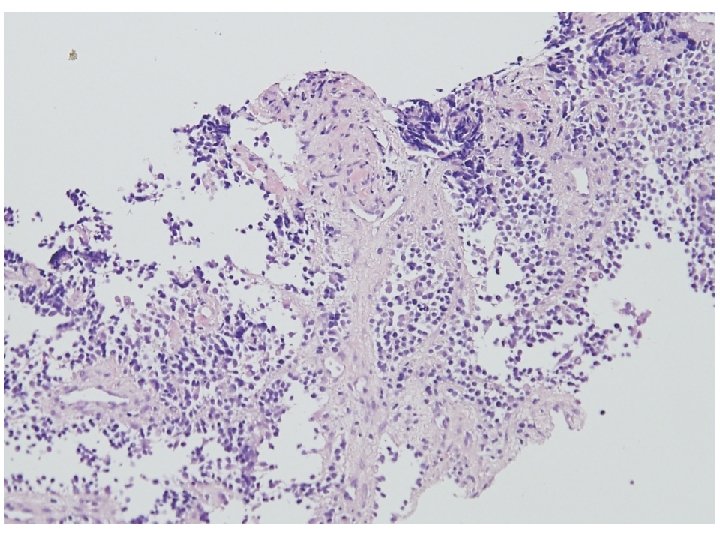

Rhabdomyosarcoma, alveolar type § Older mean ages than do the other type of RMS (adolescents) § Extremities and trunk § Worst prognosis § Histologic finding § § § Discohesive tumor cells in fibrous septa around alveoli/ spaces Multinucleated giant cells Solid variant (alveolar spaces x) § PAX 7 -FKHR –favorable course

Cytologic morphology of RMS • A limited number of studies (250 cases) have attempted to characterize the cytologic morphology of RMS. • Embryonal subtype of RMS – Predominantly composed of primitive round cells with rounded nuclei – Spindle-shaped cells, large, tadpole or ribbon-shaped cells – Anisocytosis – Intranuclear or cytoplasmic inclusion • Alveolar subtype of RMS – Completely dissociated cells or clustering – Small and lymphocyte-like, presenting fine granular chromatin – Binucleated or multinucleated cells